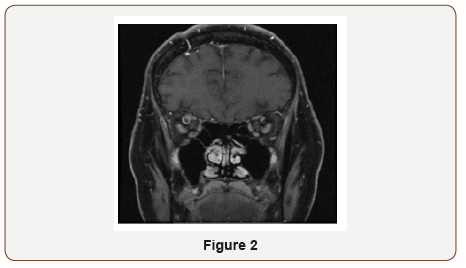

On physical examination, pupils were equal and reactive to light (4 mm in dark, 2 mm in light). Extra ocular movements were intact. She had binocular diplopia and proptosis of right eye. Rest of the neurological exam was normal. Hematological workup was negative for hypercoagulability state. The patient was started on heparin per stroke protocol with recommendation of discharging on Coumadin. Gradual resolution of symptoms was noted after 4 day (Figure 1 & 2).